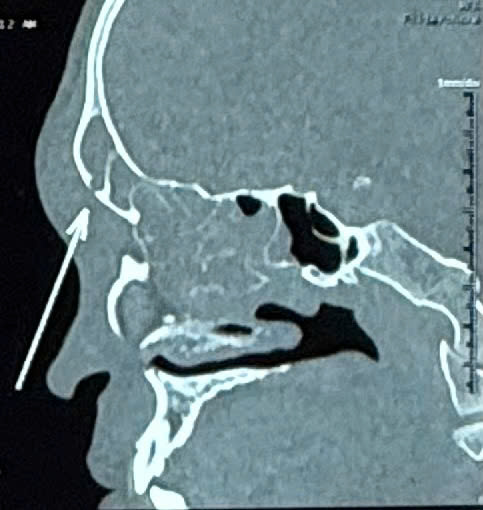

Kết quả chụp CT mũi xoang cho thấy tình trạng viêm đa xoang rõ rệt, đặc biệt bên phải

Kết quả chụp CT mũi xoang cho thấy tình trạng viêm đa xoang rõ rệt, đặc biệt bên phải. Hình ảnh học ghi nhận tổn thương lan từ xoang trán phải ra phần mềm vùng trán, kèm theo khuyết xương thành trước xoang trán. Đây là biểu hiện điển hình của biến chứng Pott's Puffy Tumor - một dạng viêm xương trán kèm áp xe dưới màng xương.